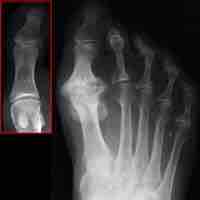

As individuals age, bone resorption can outpace bone replacement, which can lead to osteoporosis and fractures.

In osteoporosis, bone mineral density (BMD) is reduced and the integrity of bone proteins is altered, increasing the risk of fracture.